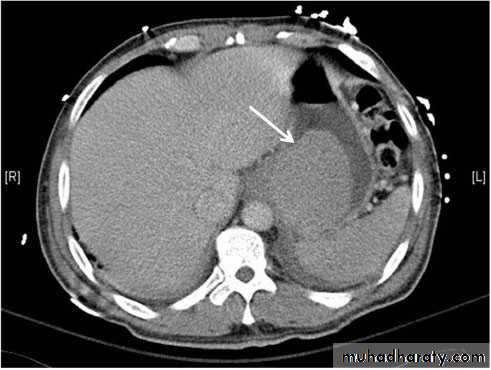

CT : IV contrast is usually given to emphasize the density between normal parenchyma and pathological lesions. The liver has dual blood supply from hepatic artery and portal vein. The liver is divided into 8 segments determined by hepatic and portal veins. The normal liver is higher or equal in density to the spleen. The normal intrahepatic bile ducts are not visible.

At CT, metastases are seen as rounded areas, usually lower in density than normal liver parenchyma with intense enhancement seen after IV contrast.

CT is more sensitive and specific. Lacerations and hematomas are recognized as low density areas relative to the normal intact, enhanced parenchyma. Leakage of contrast indicate active bleeding

Fatty infiltration of the liver

It is a frequent finding, particularly in those with hypercholesterolaemia, obesity, diabetes or those who take alcohol to excess. It may involve the whole liver or it may just involve individual subsections

At CT, liver density is less than splenic density